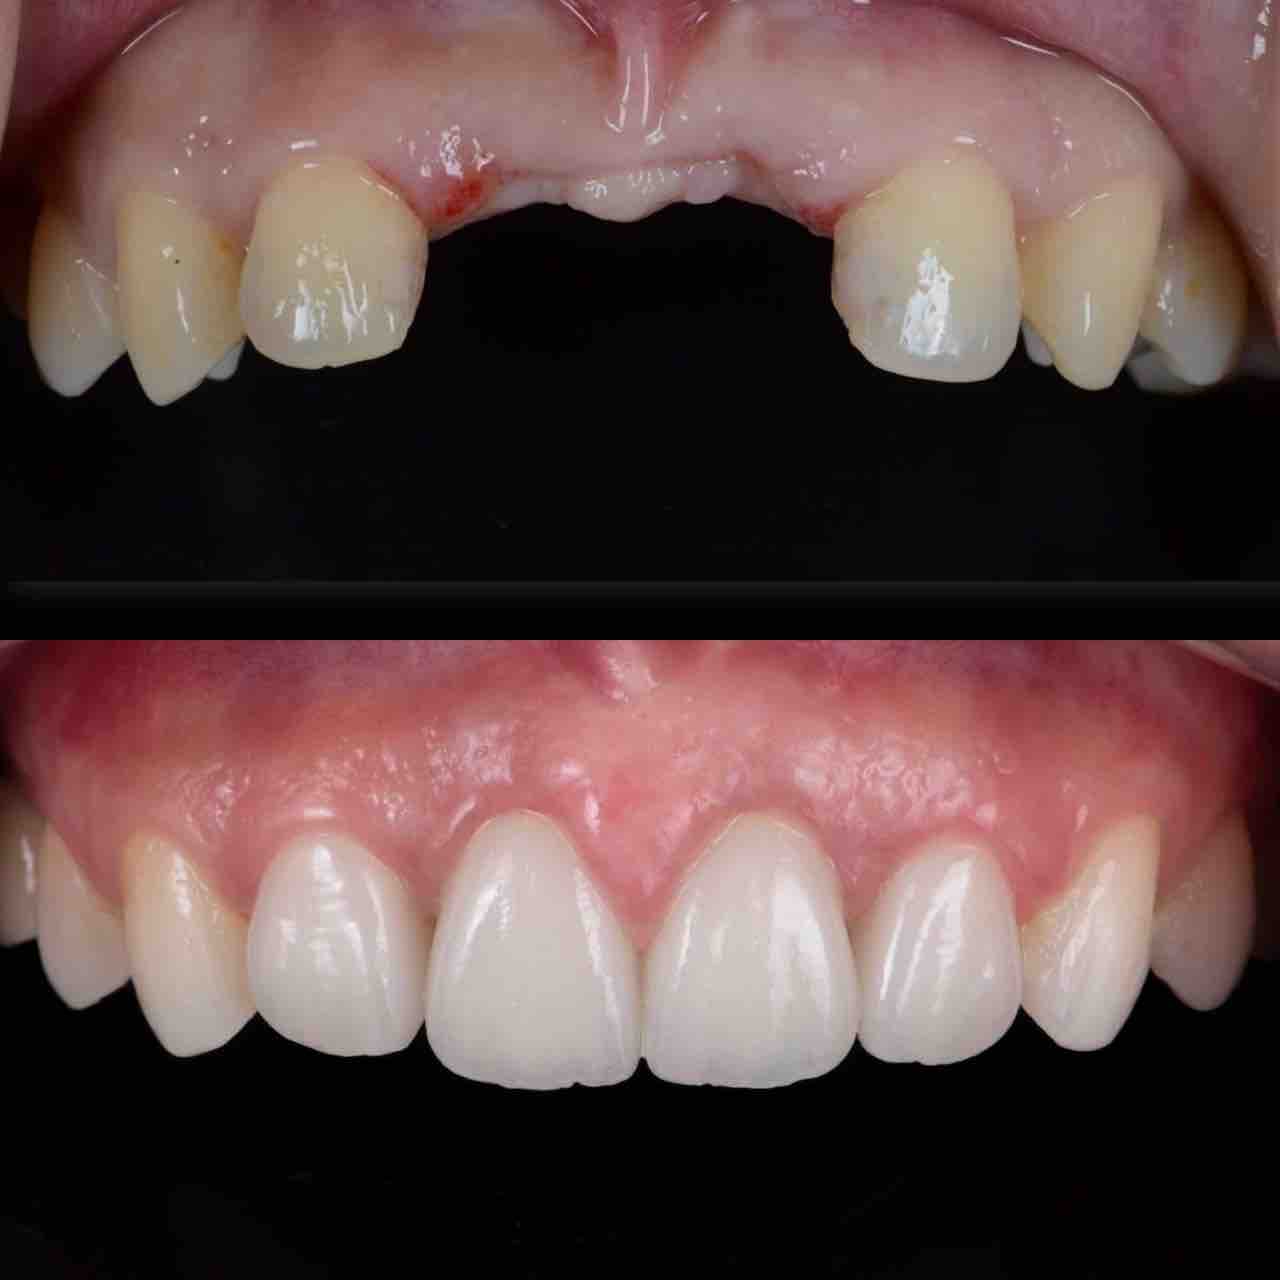

¥¤¥ó¥¹¥¿¥°¥é¥à¤ËºÜ¤»¤Æ¤¤¤ëÅö±¡¤Î¾ÉÎã¤Ç¤¹

ðÌî»õ²Ê¾ÉÎ㢠ÀèÅ··ç»¶ºÀµ¥¤¥ó¥×¥é¥ó¥È

ðÌî»õ²Ê¾ÉÎã¡¶ºÀµ¥¤¥ó¥×¥é¥ó¥È¥»¥é¥ß¥Ã¥¯